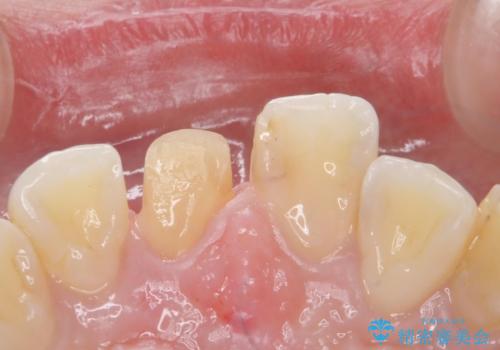

- 前歯のかぶせ物の色が気になるとのことで来院された患者様です。

セラミッククラウンで作り変えていきます。